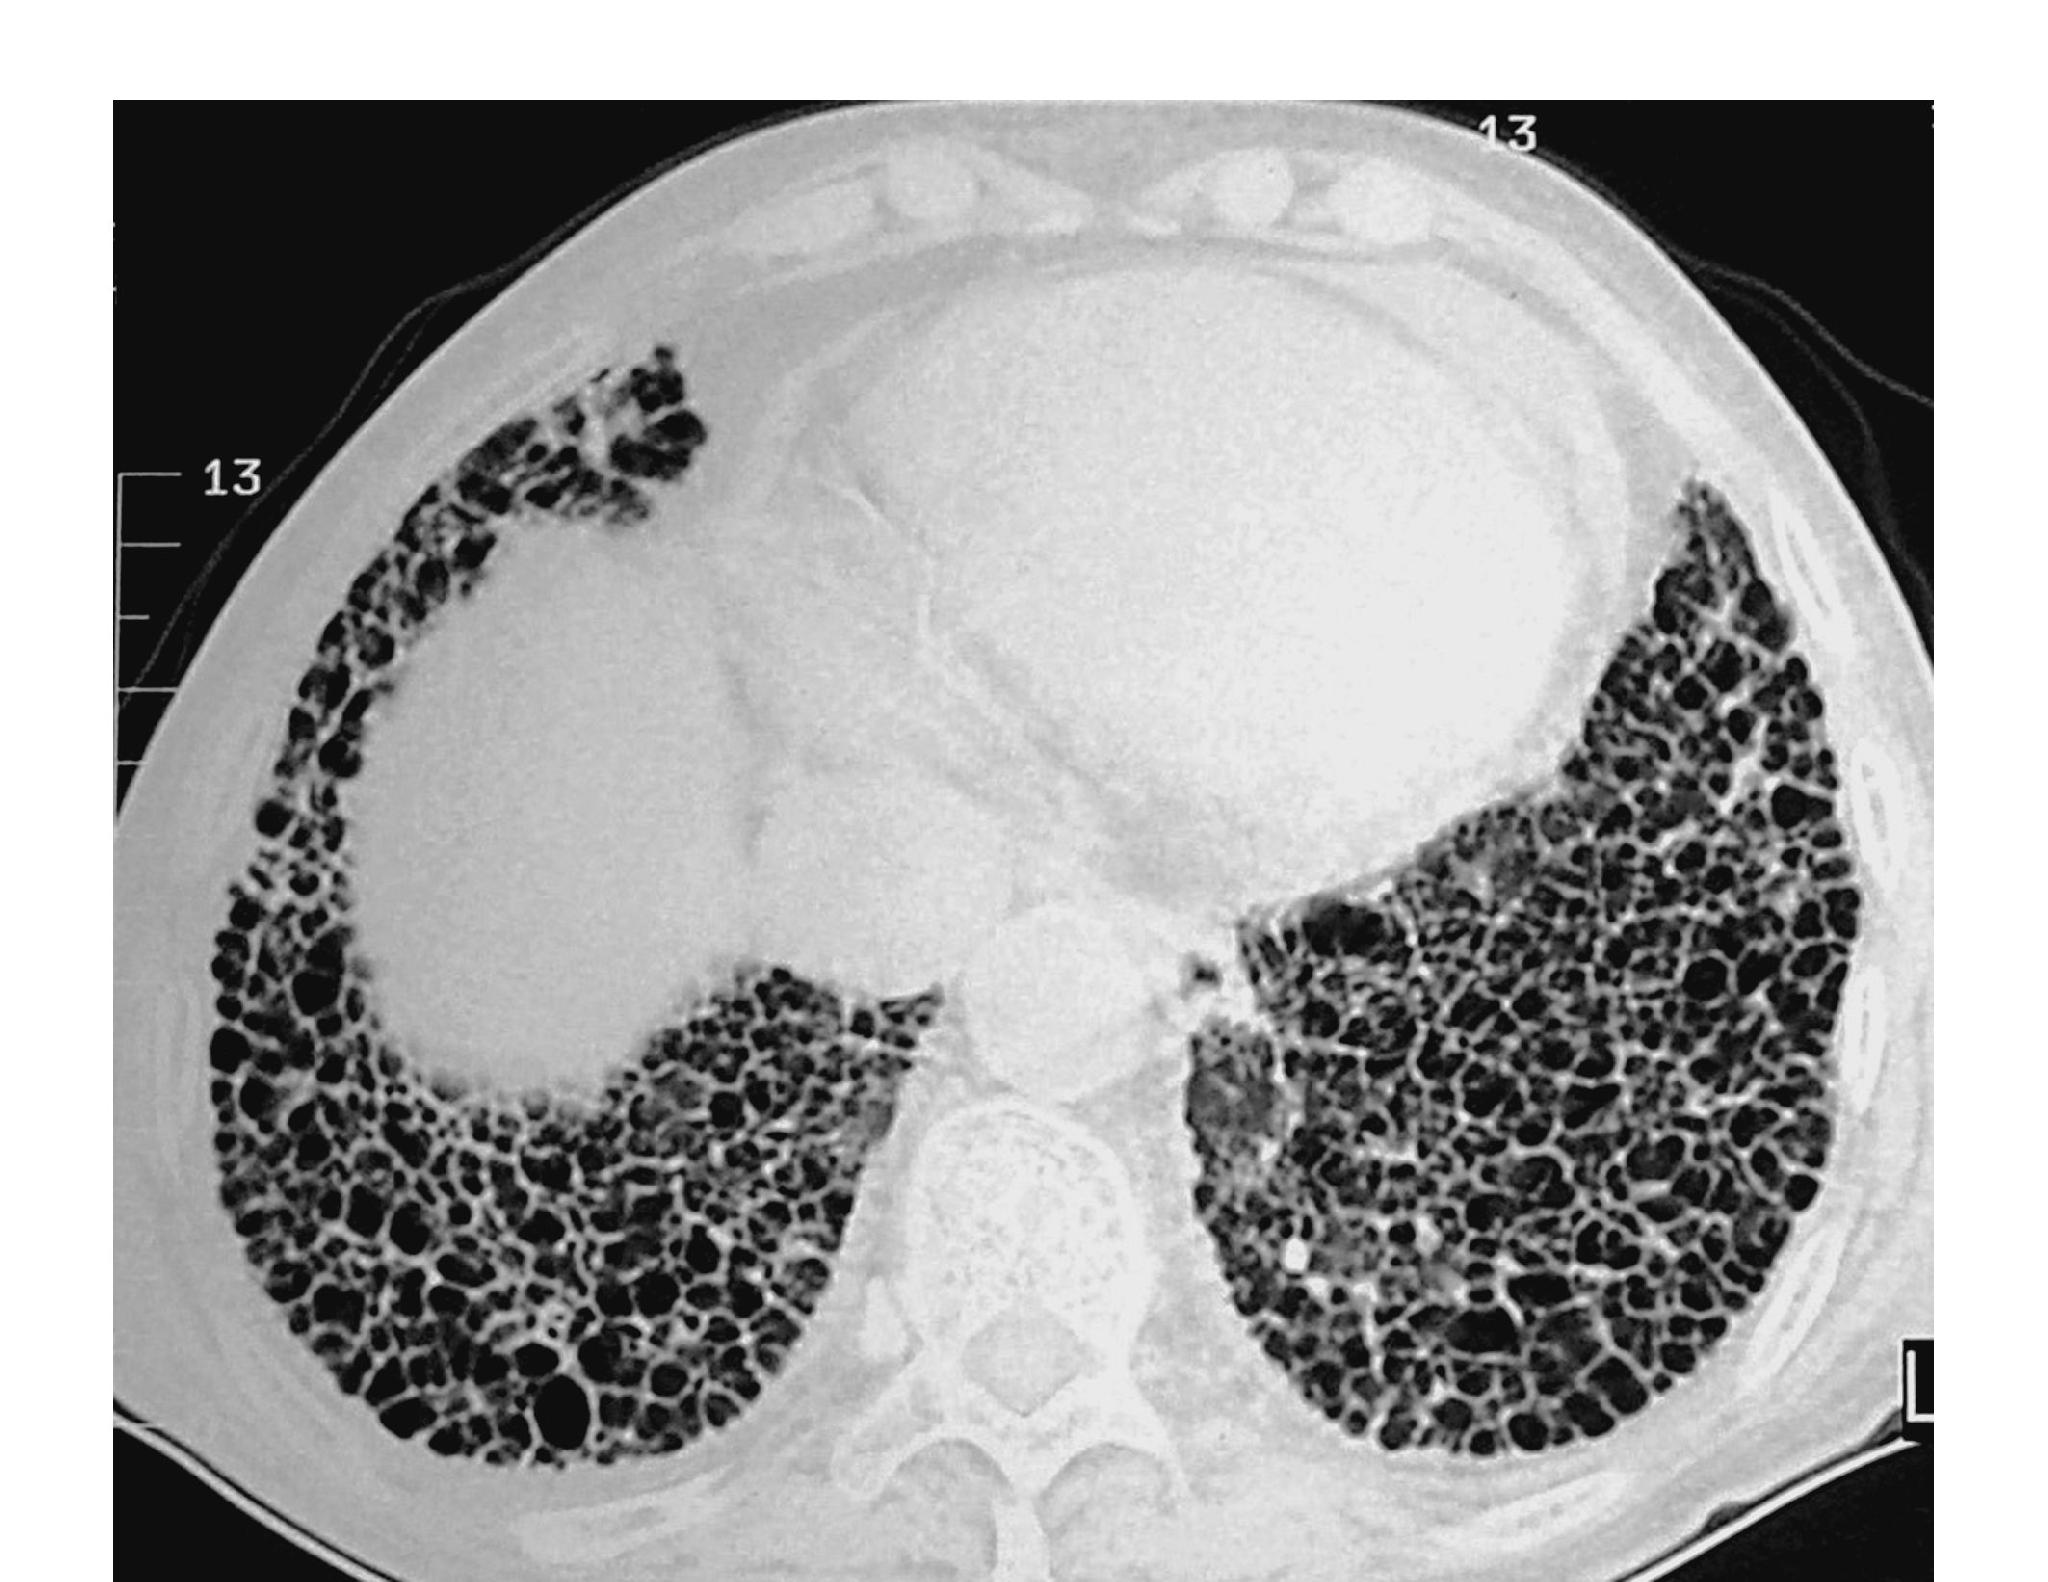

肺间质纤维化,患者的肺部就如长了“瘢痕”,是由很多原因引起的弥漫性肺间质破坏、瘢痕形成的一种呼吸道疾病。

这种广泛的肺部瘢痕导致氧气不能顺利进入肺部血管,可导致肺功能出现不可逆转的减退,出现呼吸困难和全身缺氧的症状。